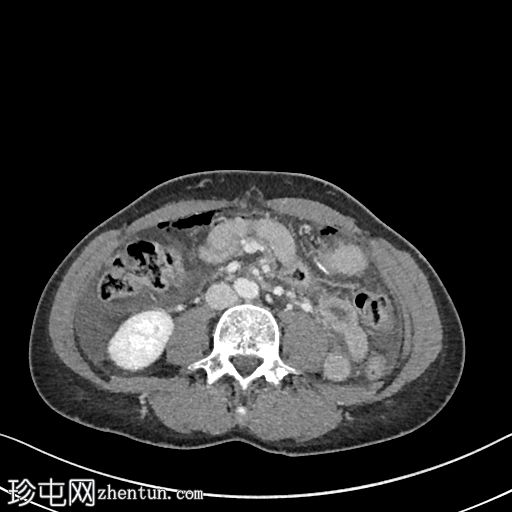

轴位增强扫描(门静脉期)

大量游离液体和游离气体。游离气体回流至邻近的胃空肠吻合口,伴有肠壁缺损和小肠壁增厚。

漩涡征和肠系膜静脉淤血。左下腹和盆腔内可见肠壁增厚但强化的小肠袢。